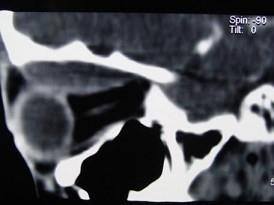

问题 男,12岁,有脓涕数年,发热约十天,伴右眼球向外下突出,CT如图,应诊断为 ( )

选项 A、眼型Graves病 B、肌炎型炎性假瘤 C、骨髓炎 D、骨膜下脓肿 E、转移瘤

答案 D